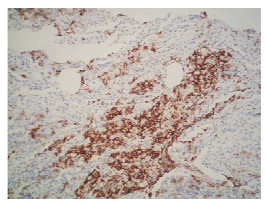

肺郎格罕细胞组织细胞增多症1例